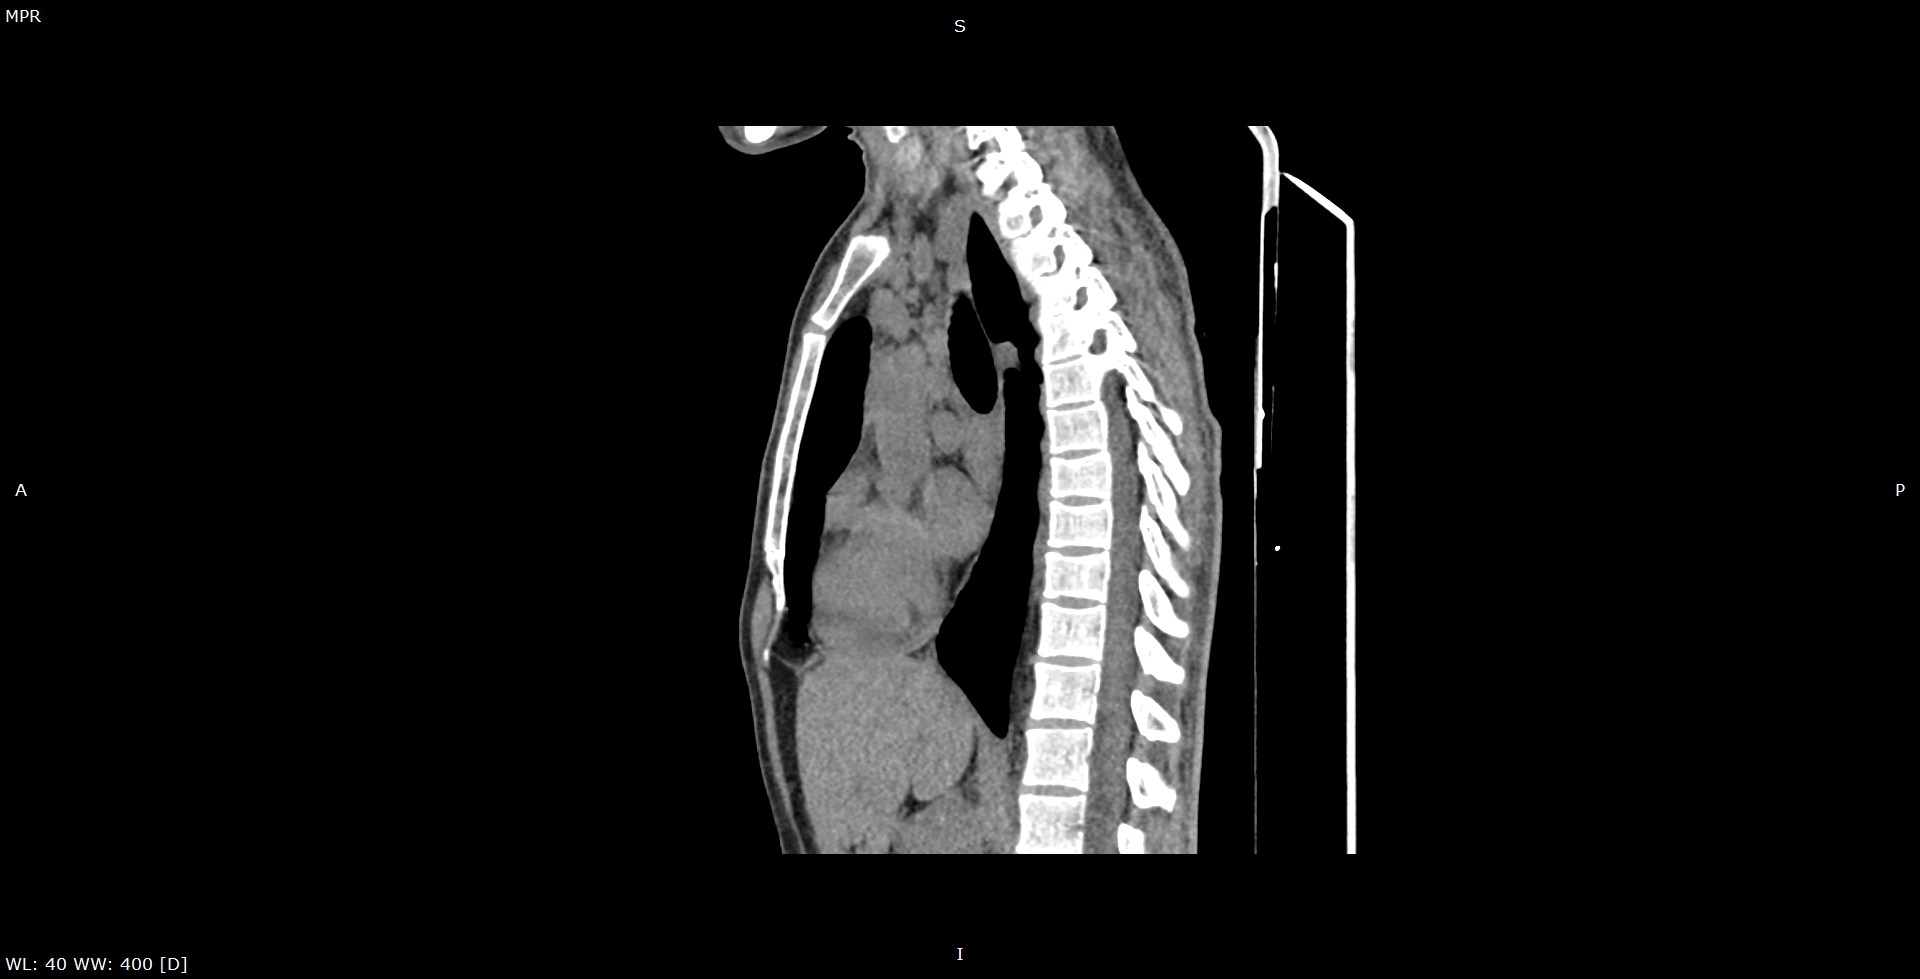

Мультиспиральная КТ лимфатических узлов направлено на изучение структуры лимфоузлов и их взаимоотношения с близлежащими органами и окружающими тканями. Исследование проводится прицельно в той области, где имеются увеличенные болезненные или безболезненные лимфатические узлы.

В клинике «Доступная медицина» исследование проводится на современном компьютерном томографе экспертного класса TOSHIBA AQUILION CXL, производящего большое количество тончайших срезов исследуемой зоны и преобразующего полученные данные в 3D-изображения высокой четкости и контрастности. Аппарат оснащен большим количеством высокочувствительных детекторов, которые улавливают сигналы при сканировании за несколько секунд, что существенно сокращает время исследования и снижает лучевую нагрузку на организм пациента.

При необходимости выявления злокачественной инфильтрации лимфоузлов, исключения их метастатического поражения проводится КТ лимфоузлов с контрастным усилением. Внутривенно введенный контрастный препарат, имеющий в своем составе йодсодержащее вещество, накапливается в измененных тканях и делает их более четкими для визуализации. МСКТ с внутривенным болюсным контрастированием дает возможность диагностировать онкологические процессы на ранней стадии, что имеет решающее значение для эффективного и своевременного лечения.